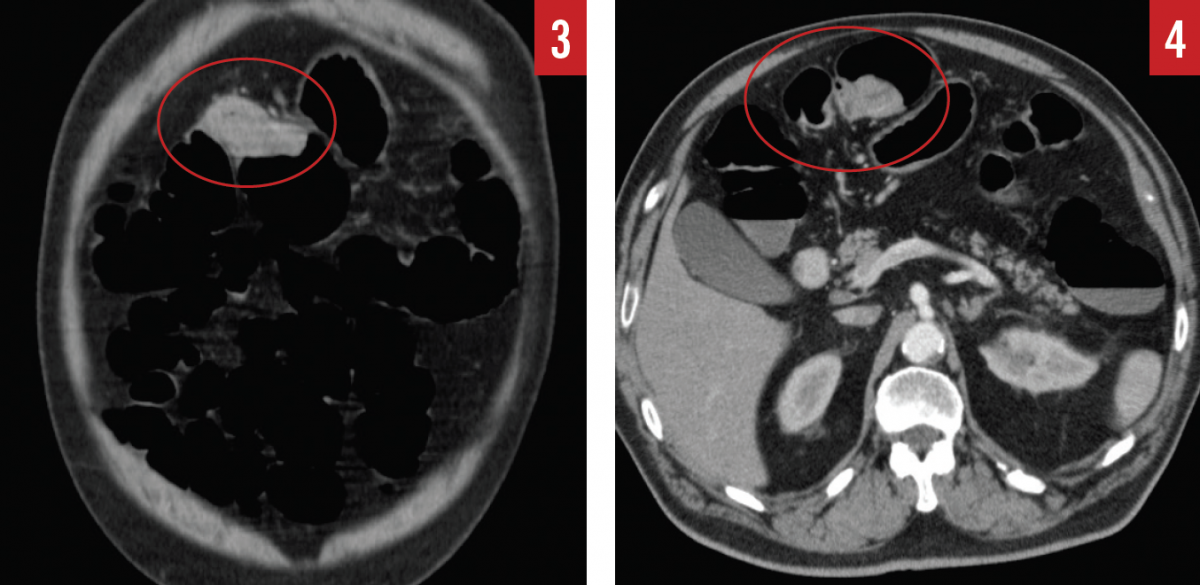

During the hemicolectomy, when the ascending colon was mobilized and palpated, the tattooing done during the colonoscopy had faded and was no longer visible due to the prolonged time between the colonoscopy and the hemicolectomy. The ascending colon was then palpated, and a firm, rubbery mass was felt within the cecum as described by CT. The ascending colon from the terminal ileum to the border of the liver was then excised and examined; however, no tumor was present within the cecum or the ascending colon, only a fatty infiltrate near the ileocecal valve. The surgeon then reviewed the CT scan and report to identify the cecal mass, at which time a mass was also noted in the hepatic flexure (Figures 2-4).

Confused by the conflicting information, the surgeon then palpated the remaining colon and felt a mass within the hepatic flexure. The hepatic flexure was then excised, and the mass was examined histologically and found to be a tubulovillous adenoma with high-grade dysplasia. It became apparent that the original mass that had been visualized on colonoscopy and that had been thought to be located in the cecum was in fact in the hepatic flexure, and during the extended time between colonoscopy and hemicolectomy, the mass had progressed from low-grade dysplasia to high-grade dysplasia.

In the example case presented here, the surgeon visualized a mass in the hepatic flexure that he perceived to be in the cecum. The CT imaging and radiology report corroborated this finding, stating that there was a cecal mass but with no mention of a mass in the hepatic flexure or in the rectosigmoid junction. Nevertheless, on second look, the hepatic flexure mass was apparent on images in all 3 viewing planes, and the rectosigmoid junction showed wall thickening that should have been flagged as abnormal for further workup, as well.